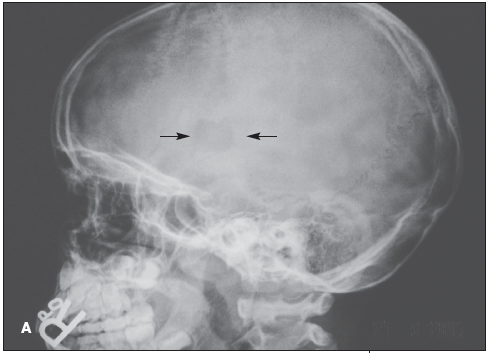

X-ray films of the skull showed a circular defect and an overlying soft tissue swelling (A). CT scans of the head confirmed the solitary bone defect in the skull without any involvement of the brain (B). The complete blood cell count was within normal limits.